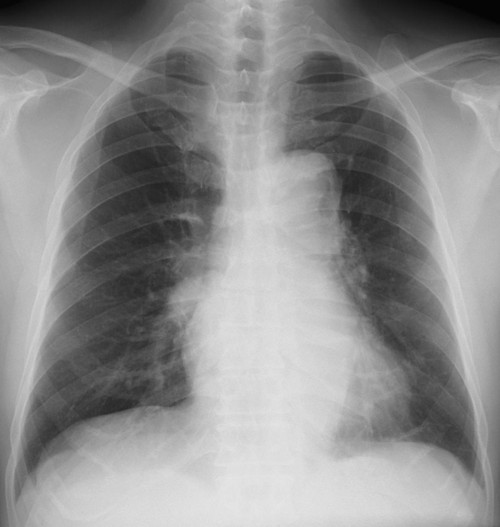

胸部大動脈の中間部が不鮮明に途切れて追うことができなくなっている(その上と下は明瞭になっている)。シルエットサイン陽性と判断すると、陰影はS6に存在すると推定可能。